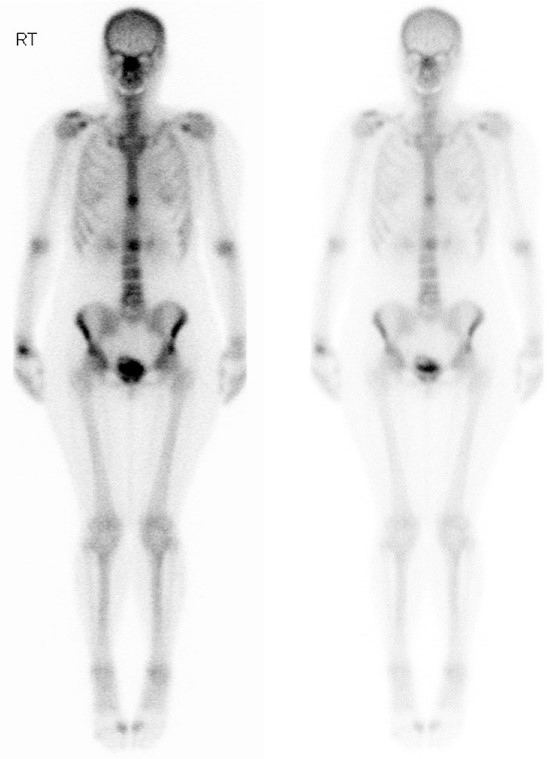

Vous avez fait réaliser une scintigraphie osseuse qui montre l’aspect suivant. Le scanner TAP confirme les localisations osseuses exclusives, hormis un nodule pulmonaire lobaire supérieur droit.

Question 12 - Concernant l’examen ci-dessus et la prise en charge que vous proposez (une ou plusieurs réponses exactes) :

Il existe en effet un hypermétabolisme bilatéral en regard des ailes iliaques.

Il s’agit de la vessie, et du produit de contraste accumulé à l’intérieur.

La choline est utilisée dans les TEP-TDM des cancers de la prostate.

Une scintigraphie osseuse nécessite l’injection de technétium 99, à la différence d’un TEP-TDM qui nécessite l’injection de 18-FDG.

La scintigraphie osseuse est un examen simple et parfois plus accessible qu’un TEP-TDM.

Elle repose sur l’injection de bisphosphonates marqués au technétium 99, qui se fixe donc dans les zones où l’activité ostéoclastique est importante, dont les métastases osseuses.